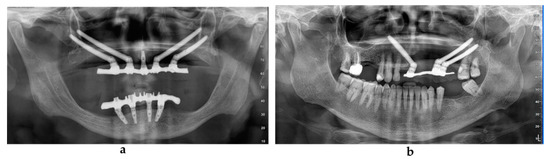

Figure 3. Post-loading radiographic evaluation in a patient with maxillary atrophy (a) and in an oncologic patient (b).

2.4. Prosthetic Procedure

After the flap closure, a sterilized rubber dam perforated at the position of the already mounted transfers was set up. The resin template that was already used for the CBCT was drilled on the palatal side to allow the placement of the transfers. The screw-retained transfers were splinted together using inlay pattern resin (Duralay, Reliance, Worth, TX, USA) The resin template was also used as an impression tray. The impression was made using polyether material injected through the free spaces using a carrier syringe. Very short transfers were chosen to keep the template (reproducing the previously evaluated prosthesis) in occlusion during the setting of the impression material. After transfer removal, healing abutments were positioned onto the implant connections and the impression tray was sent to the technician. After 48 h, a metal framework with the front teeth and the occlusal plate in position was evaluated intraorally. After 72 h, the final provisional screw-retained prosthesis was evaluated intraorally and delivered. In some cases, where the framework check was incorrect, the prosthesis delivery was delayed by approximately 120 h. In addition, radiographic evaluation was performed after loading (Figure 3a,b).